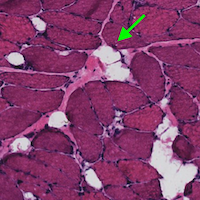

Our mission is to conduct high impact, translational research in the field of musculoskeletal research. Although our core focus is in skeletal muscle design and plasticity, we will continue to explore leading-edge questions in Radiology, Regenerative Medicine, and Rehabilitation.

Regenerative Medicine